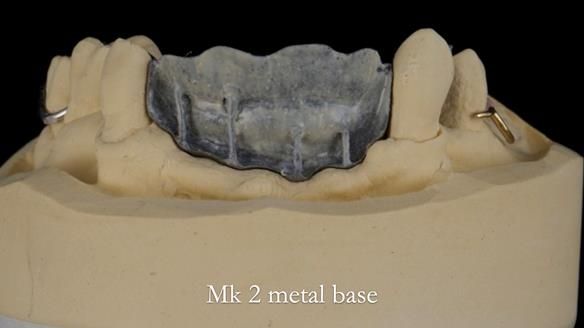

Jean’s Class I Mod III RPD: Learning from My Mistakes – From a Fractured Mk1 to a Stronger Mk2 (4 Years On)

In this edition, I present the removable partial denture treatment for Jean, an 80-year-old woman with a sore mouth caused by a soft tissue-supported 'gum stripper' acrylic denture and a clenching habit. Below, I outline the step-by-step process of her treatment. It wasn't straightforward; I had to remake the denture after it fractured to achieve a satisfactory result. Each patient is unique, and sometimes a new RPD serves as a prototype. Occasionally, I need to make adjustments, learn from any mistakes, and refine the design to get it right.

The treatment has been a success over the past 4 years.